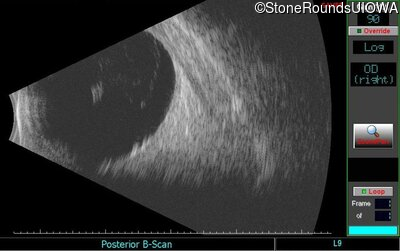

B-Scan Ultrasonography - Right - Count Fingers 2'

Exemplar